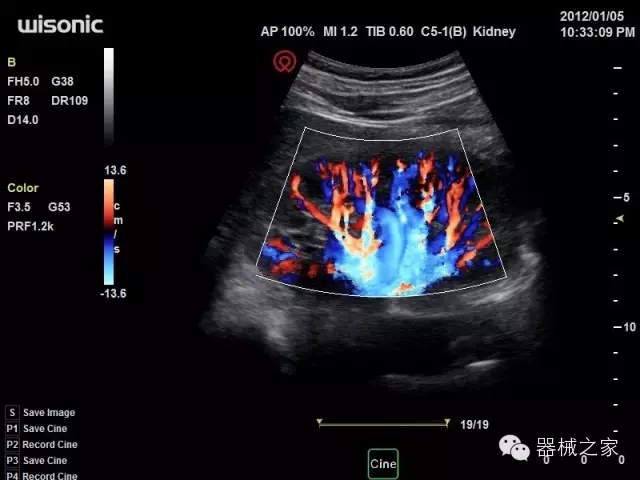

臨床圖片賞析

產(chǎn)品特點

·全球目前唯一一款配備主機雙探頭接口,整機重量(含電池)在5公斤以內(nèi)的便攜式彩超;

·一款互聯(lián)網(wǎng)彩超,只要有手機信號的地方就可以非常方便地實現(xiàn)遠(yuǎn)程會診和病案調(diào)取;